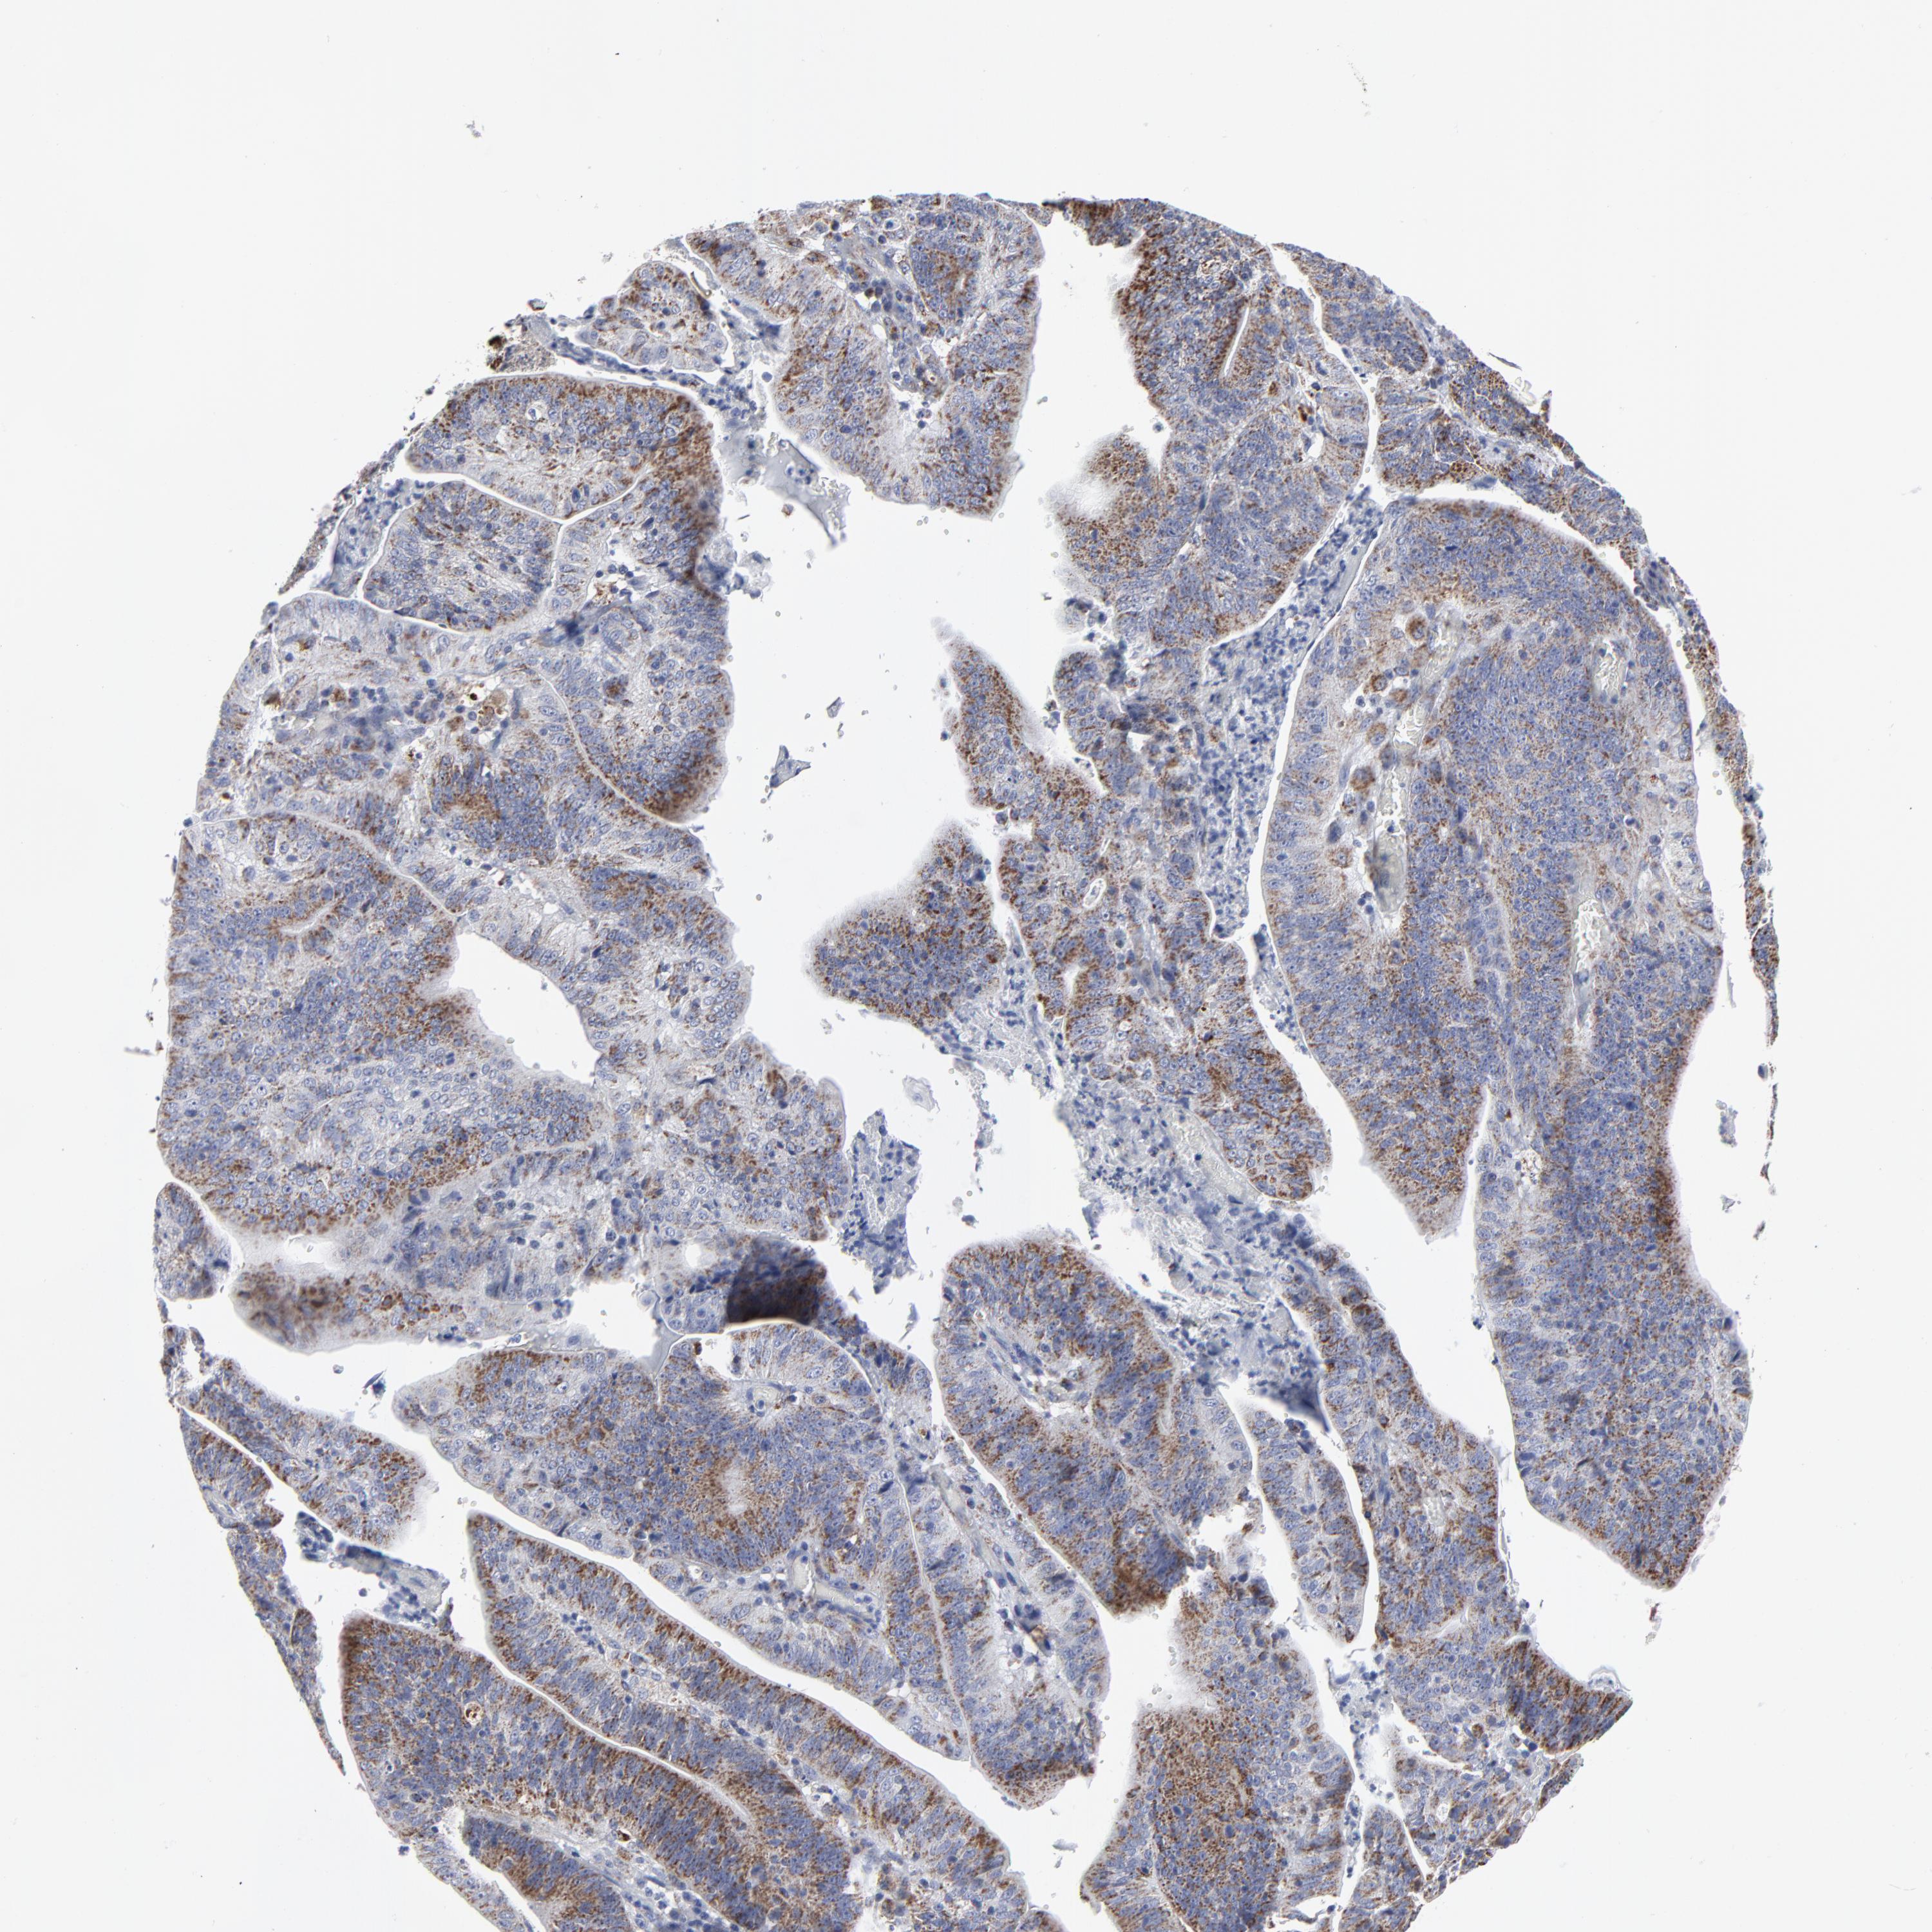

STOMACH CANCER - Protein expressioni

A mouse-over function shows sample information and annotation data. Click on an image to view it in a full screen mode. Samples can be filtered based on level of antibody staining by selecting one or several of the following categories: high, medium, low and not detected. The assay and annotation is described here.

Note that samples used for immunohistochemistry by the Human Protein Atlas do not correspond to samples in the TCGA dataset.

Antibody stainingi

Antibody staining in the annotated cell types in the current human tissue is reported as not detected, low, medium, or high, based on conventional immunohistochemistry profiling in selected tissues. This score is based on the combination of the staining intensity and fraction of stained cells.

Each image is clickable and will lead to virtual microscopy that enables deeper exploration of all samples and also displays staining intensity scores, fraction scores and subcellular localization as well as patient and tissue information for each sample.

Antibody HPA003323

Antibody CAB002007

Staining

High

Medium

Low

Not detected

Intensity

Strong

Moderate

Weak

Negative

Quantity

>75%

75%-25%

<25%

None

Location

Nuclear

Cytoplasmic/membranous

Cytoplasmic/membranous,nuclear

Adenocarcinoma, NOS